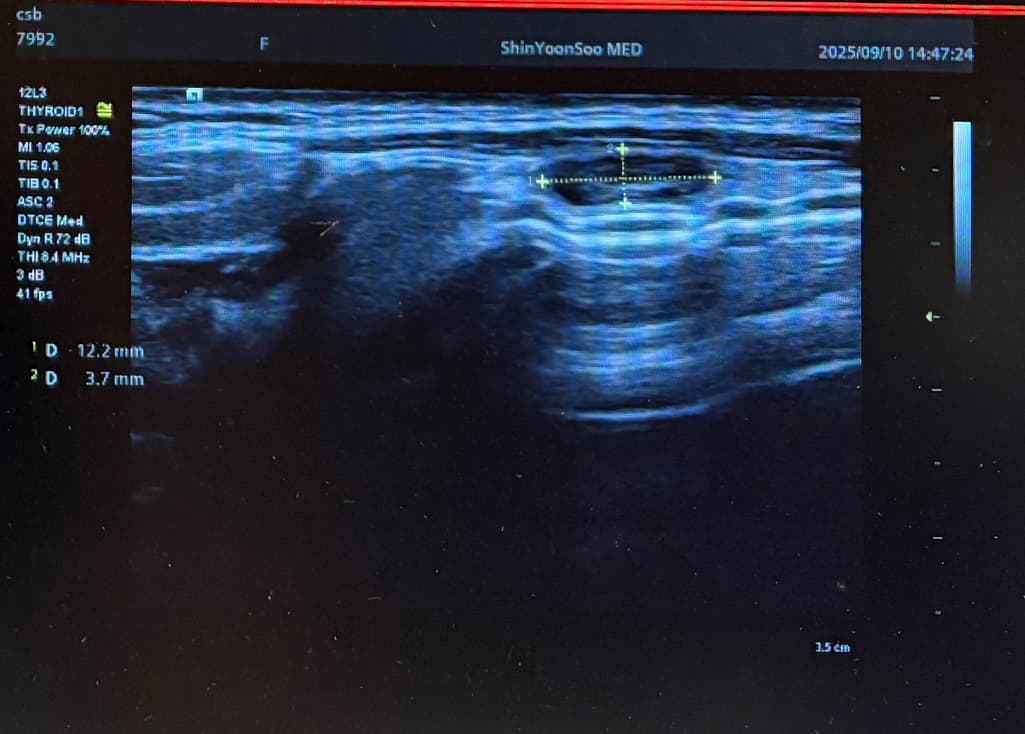

Lt 1ower lobe

1.88x1.4x2.84cm mixed nodule Lt middle lobe 1.22x0.37x 0. 49cm의 nodule 소견으로(의뢰서에 적혀있던 내용) 초진 보러가니 초음파 사진만 보시고는 식도와 신경에 들러붙어있고 점점점 커지면서 추후엔 응급수술로 진행될 수 있으니 아직 젊을때 빠르게 수술로 떼어내자고 결론은 수술밖에 없다고 냅다 수술일정 한달뒤로 잡고왔습니다.

왼쪽에 약 3cm가량으로 전체가 혹일거라며 상황이 많이 안좋은거고 위치가 안좋다고 하셔서 다음주에 수술전 검사 받은 후 2주뒤 입원으로 일정이 잡혔는데 보통 세침검사 또는 총생검사 후 수술 여부가 결정되는걸로 알고있는데 ..